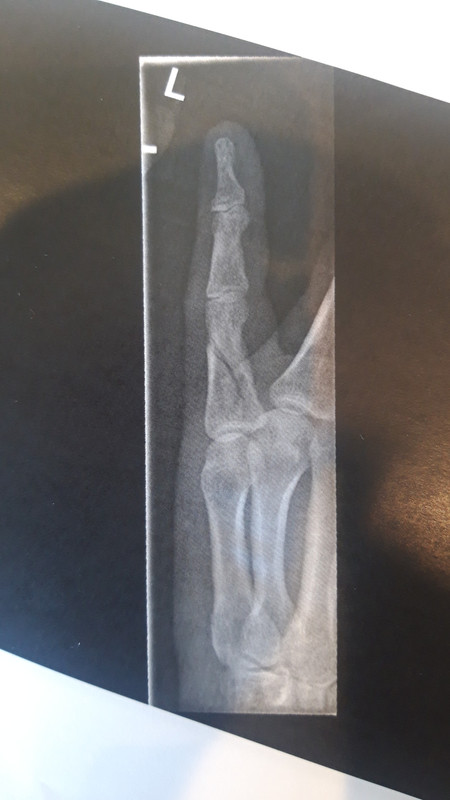

The fracture looks fairly uncomplicated and non-displaced, so unlikely to need surgery, but I'm not an ortho. You're already on the right pathway (you attend fracture clinic, they refer you to physio). Fingers are a lot more prone to stiffening up than other joints, it's frightening how fast it can happen sometimes, and they are also incredibly important for our interaction with the world, so make sure you attend your fracture clinic and physio

All good advice, thanks. Yes, out of area (England/Scotland). It's a spiral fracture which Dr Google says will heal in 3 to 4 weeks. Yes pinky. Had one of our Cubs do something similar on a weekend camp which we taped a stick to. Turned out his mum was a nurse and, fortunately, approved, except best advice is to strap it to the neighbouring finger. Now know that you avoid taping the joints, due to swelling.

Fracture clinic today, seen by xray then consultant then physio in fairly short order. Physio not impressed by Minor Injuries 'strap it and she'll be right' and would have had it in a splint from the get go. Today's xrays showed it's still properly broken, but that's because the bone knitting doesn't show. Now sporting a hand crafted thermoplastic sheath in the same blue as the physio's shirt but only for another week or so. Only got three nights left to do April's BAM though so it'll needs be a local one.